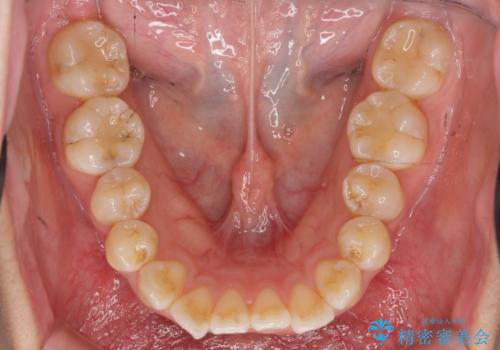

- 前歯の噛み合わせの開きの改善を求めて来院されました。

奥歯はほとんど動かさず(奥歯の噛み合わせはほとんど変えず)前歯のIPR矯正でガタつき前突感(出っ歯感)の改善を計画します。

ほとんど前歯のみの矯正治療であることからトータル14枚のマウスピースで並べるインビザラインライトによる治療を行います。